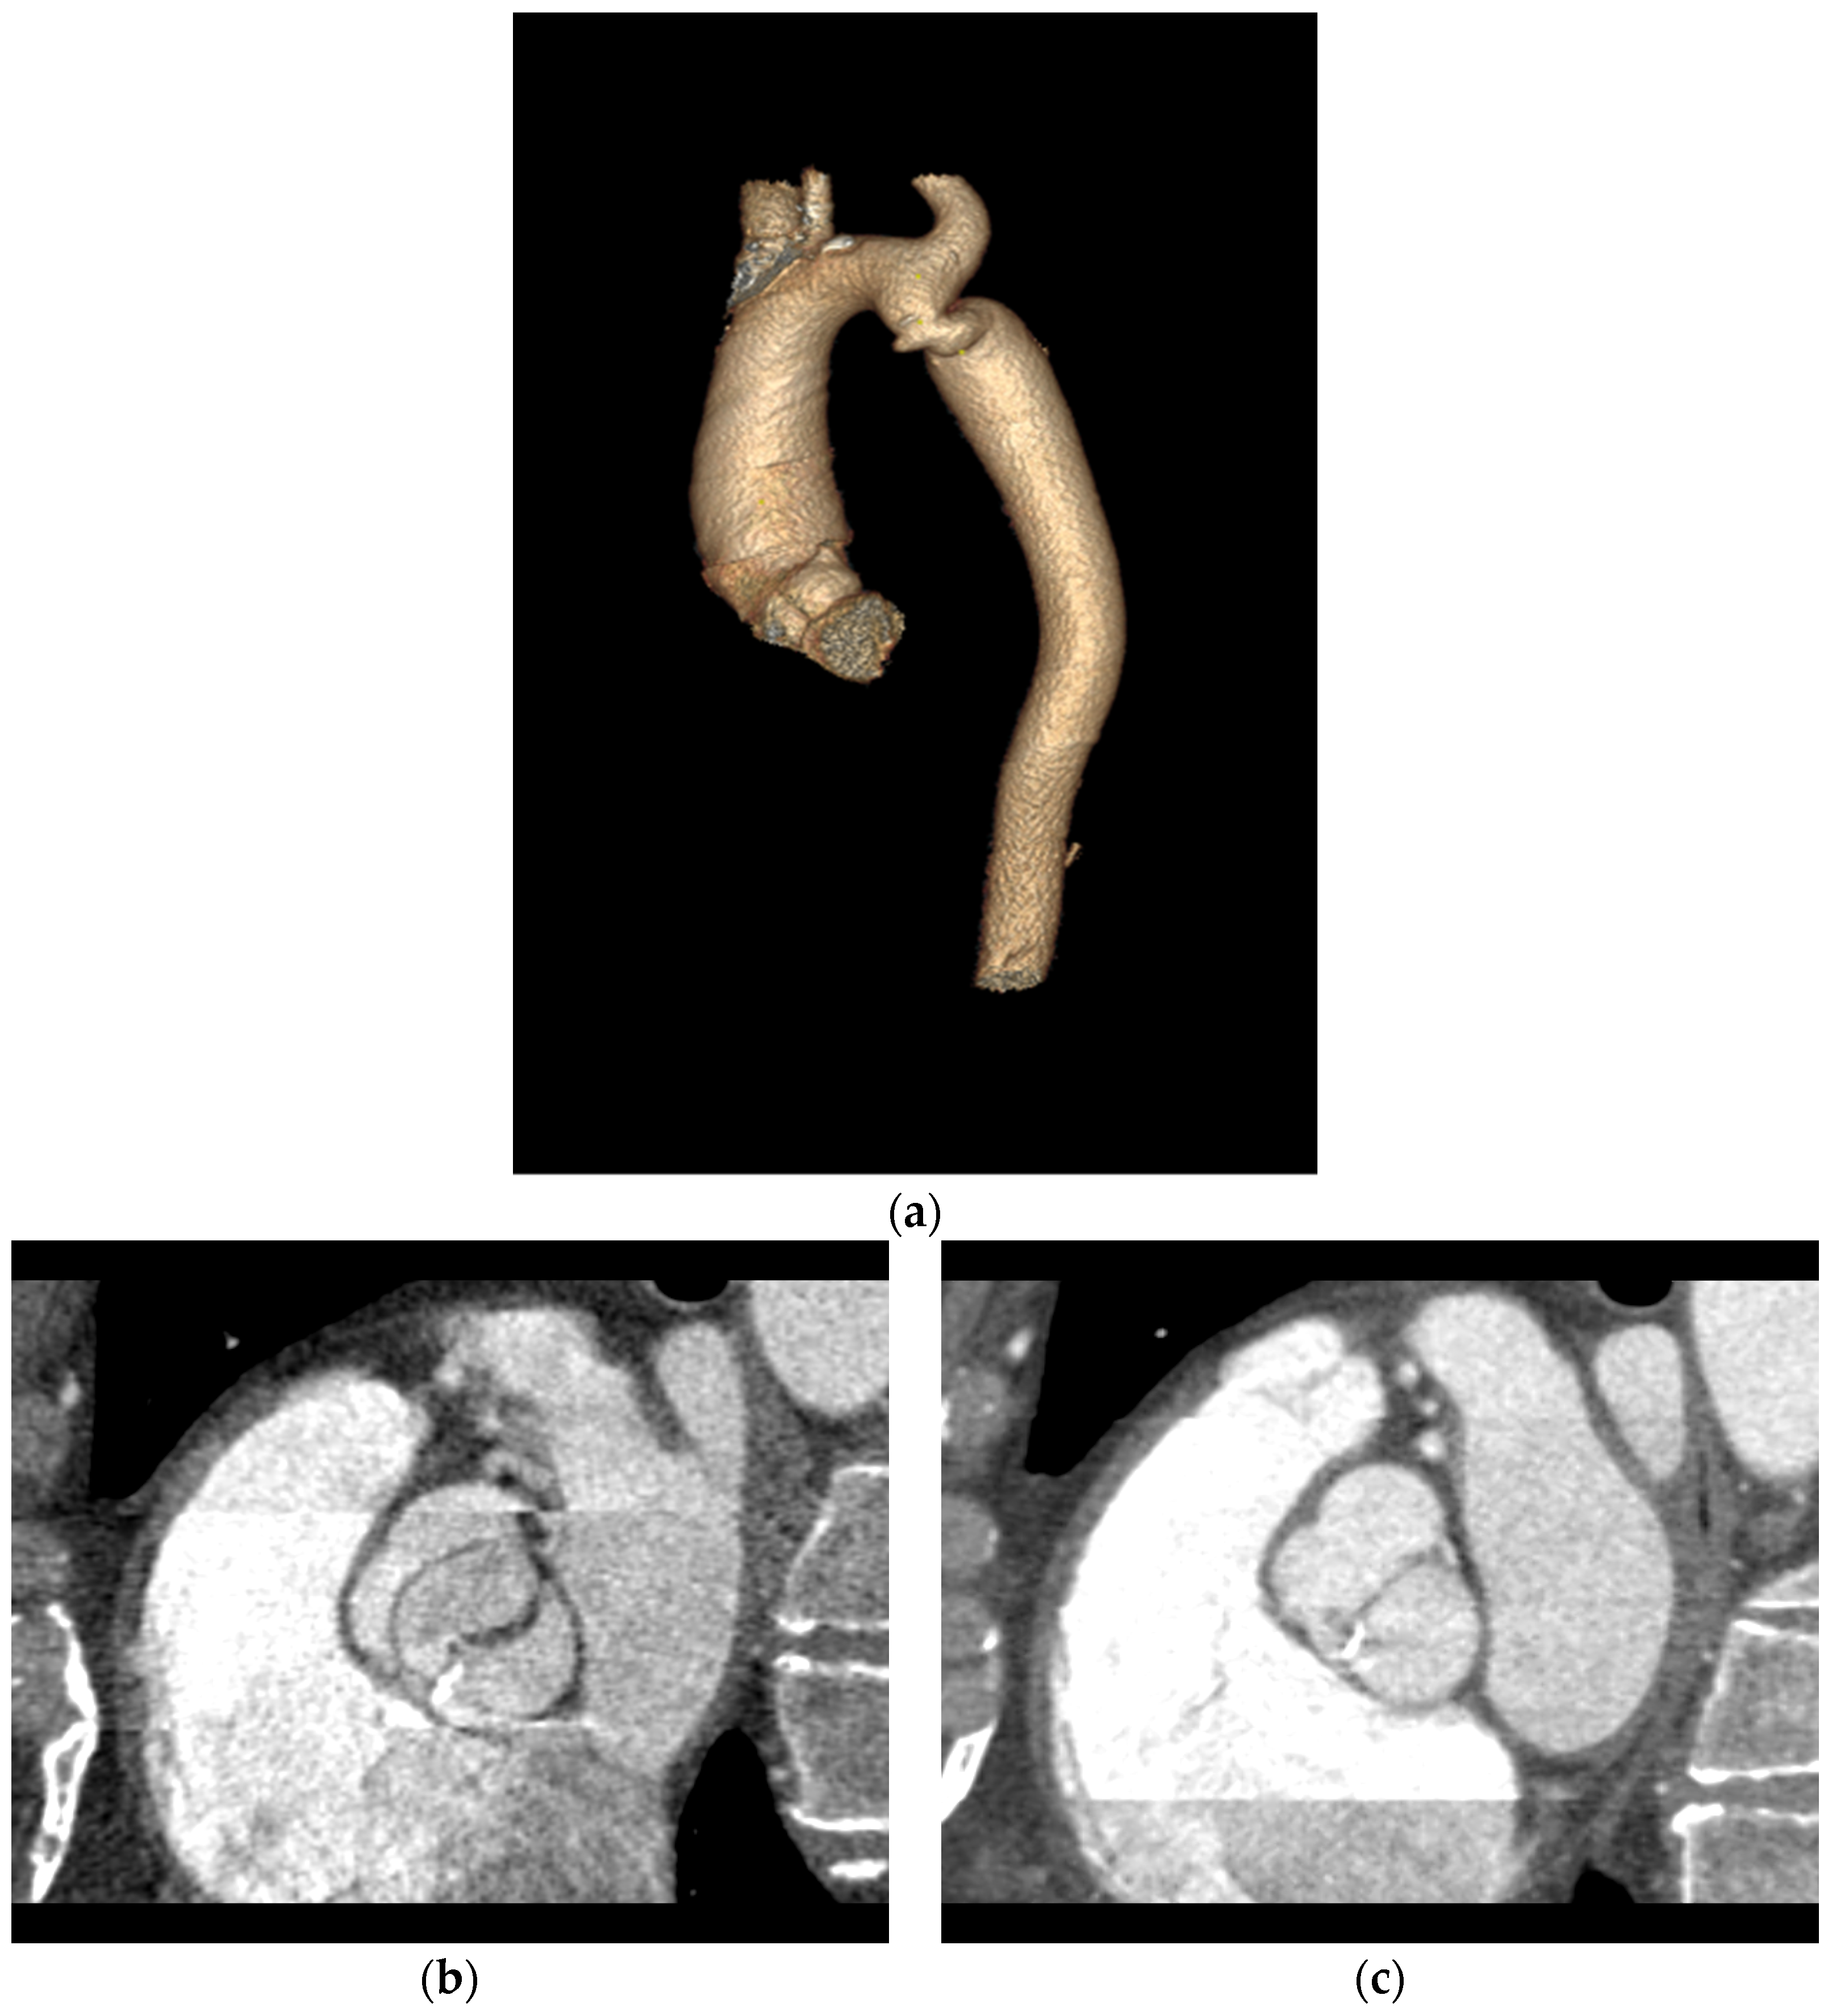

Patients with a Bicuspid Aortic Valve (BAV) Diagnosed with ECG-Gated Cardiac Multislice Computed Tomography—Analysis of the Reasons for Referral, Classification of Morphological Phenotypes, Co-Occurring Cardiovascular Abnormalities, and Coronary Artery Stenosis

2.2. Computed Tomography Protocol